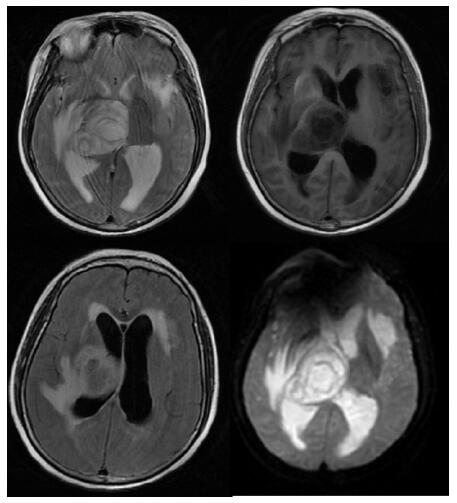

患者,女,54岁,工人,因“头晕5 d”于2019年9月29日至浙江大学附属第二医院急诊就诊。5 d前患者无明显诱因出现头晕,伴行走不稳、四肢乏力,无发热、咳嗽咳痰、胸闷气促、恶心呕吐、四肢抽搐等,未就诊。我院急诊头颅磁共振(MRI)示:右侧丘脑及左侧岛叶异常信号,局部累及右侧中脑(图 1),考虑脑多发占位性疾病。在急诊抢救室予甘露醇100 mL静滴脱水降颅压等对症治疗,5 h后患者逐渐意识模糊。急查血常规:白细胞16.1×109/L,中性粒细胞百分比73.4%;头颅CT示右侧丘脑、左侧岛叶病变,伴脑室扩张(图 2);急诊行“双侧脑室外引流术”,术中引流液呈淡血性。术后诊断:⑴(右侧丘脑)颅内占位性病变,脓肿首先考虑,肿瘤需排除;⑵脑积水;⑶脑疝。患者带气管插管转入ICU进一步治疗。当时体温38.3℃,脉搏99次/min,呼吸频率24次/min,血压169/87 mmHg(1 mmHg= 0.133 kPa),颈软,神志昏迷,右侧瞳孔3 mm,左侧瞳孔2.5 mm,对光反射迟钝。双肺呼吸音粗,可闻及少量啰音。左侧病理征阳性。患者3个月前曾因“反复胸闷气促伴发热1个月余”在本院风湿科住院,当时胸部高分辨CT示两肺间质性肺炎、下叶为著(图 3);血化验示血沉偏高,抗心磷脂抗体阳性;诊断为“间质性肺炎”,住院期间予甲泼尼龙40 mg/d静滴×8 d,60 mg/d静滴×6 d,共住院14 d;出院后予口服甲泼尼龙40 mg/d联合雷公藤多苷片每次20 mg,一日2次治疗;此后规范于本院门诊复诊。本次起病前2个月甲泼尼龙已减量至36 mg/d口服治疗。

| 右侧丘脑及左侧岛叶异常信号,局部累及右侧中脑 图 1 患者2019-09-29头颅MRI平扫+黑水成像 |